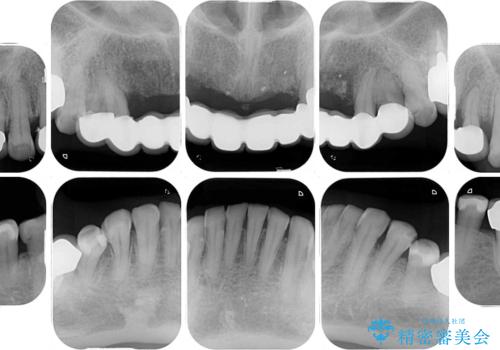

診査の結果、上顎奥歯を中心に深い歯周ポケットが認められたため、歯周ポケット除去を目的とした歯周外科処置を行うこととしました。

また、前歯のブリッジへの咬合力の負担が大きく、土台となっている歯が揺れてしまっていたため、インプラント埋入により奥歯への負担を軽減することとしました。